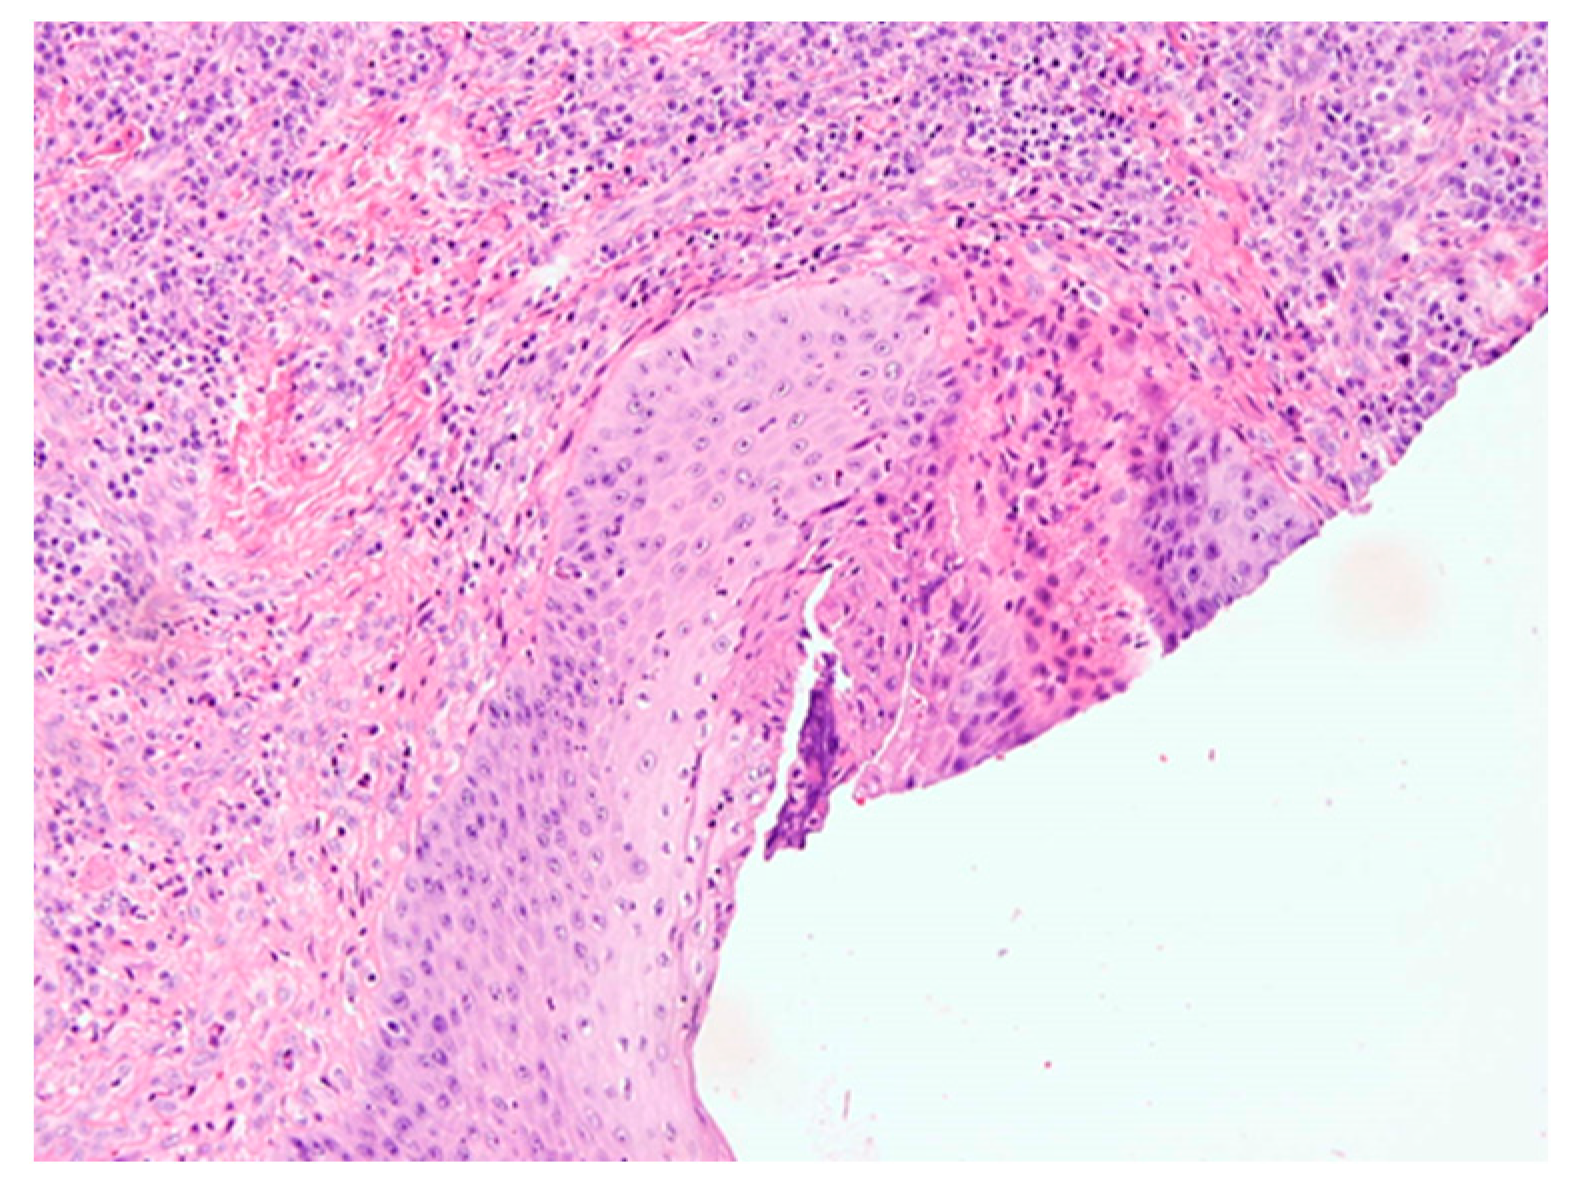

4.3. Histopathological Examination